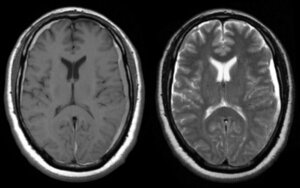

Hydrocephalus

Hydrocephalus is a build-up of fluid on the brain. The excess fluid puts pressure on the brain, which can damage it. The damage to the brain can cause a wide range of symptoms, including: headache being sick